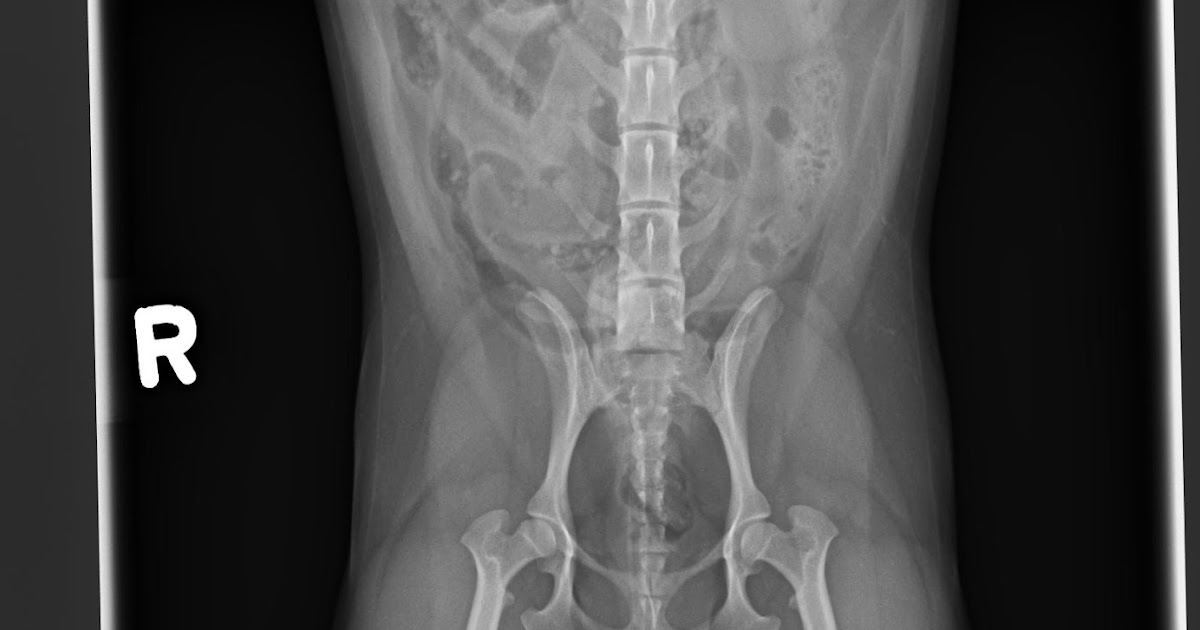

Small Animal Abdominal Radiography Today's Veterinary Practice Small Animal Radiography small animal elbow & antebrachium radiography (july/august 2012) radiographs of the carpus and manus are needed for. small animal thoracic radiography. Techniques and differential diagnoses provides a user. For any dog measuring 15 cm or greater (measured at the iliac crest), a grid (8:1, 110 lines per inch) should be used. the handbook of small animal radiology. Small Animal Radiography.